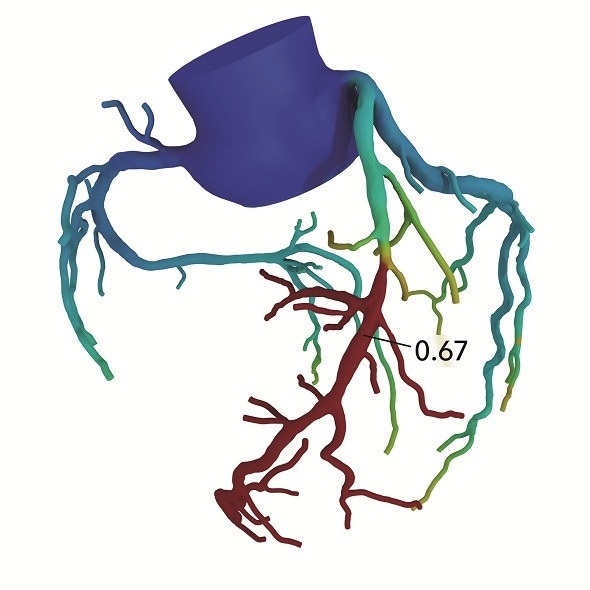

The PACIFIC study included 208 patients who each underwent a coronary CTA, SPECT, PET and three-vessel invasive fractional flow reserve (FFR) measurements. The HeartFlow Analyses were retrospectively obtained using data from the coronary CTA images. On a per-vessel basis, HeartFlow demonstrated significantly greater diagnostic performance (0.94 as measured by area under the receiver operating characteristic curve) compared to coronary CTA (0.83, p<0.001), SPECT (0.70, p<0.001) and PET (0.87, p<0.001). The HeartFlow Analysis demonstrated a diagnostic accuracy of 87%, sensitivity (or ability to correctly identify those with disease) of 90% and specificity (or ability to correctly identify those without disease) of 86% on a per vessel basis. The data were previously presented at the EuroPCR conference in May 2018.

The HeartFlow Analysis leverages artificial intelligence and highly trained analysts to create a digital 3D model of the patient’s arteries using image data taken from a standard CTA. It then applies advanced algorithms to solve millions of complex equations to assess the impact any blockages have on blood flow to the heart. The HeartFlow Analysis is provided via a secure online interface to offer actionable information to enable clinicians to determine the optimal course of treatment.